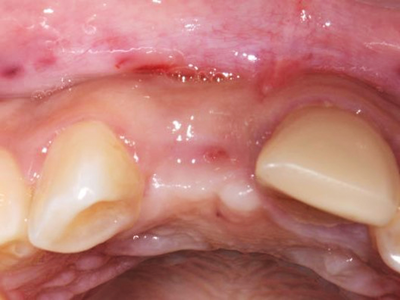

Which of the following are disadvantages of Type 1 implant placement?

There is a risk of incomplete bone fill within the peri-implant defect.

Resorption of the facial crestal bone may result in recession of the mucosa.